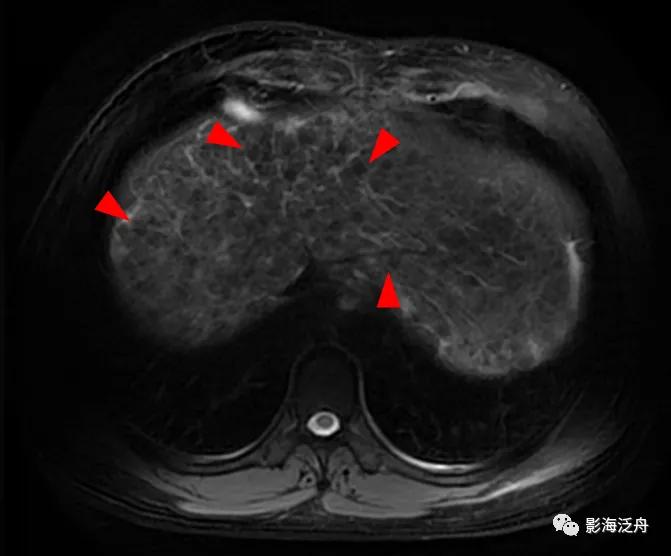

增强延时期,富纤维的肝组织呈较明显强化,而再生结节在纤维化背景肝实质的衬托下呈相对低信号(红箭标注几个较典型的再生结节)。